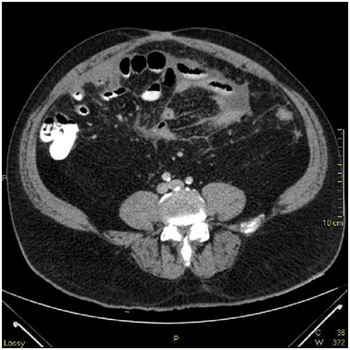

A 56-year-old Vietnam veteran man was admitted with a three-day history of worsening abdominal pain progressing into an acute abdomen. He had past medical history of Hepatitis C, diabetes mellitus, high blood pressure and chronic abdominal pain of unknown etiology. There was no gross bowel pathology by upper endoscopy or colonoscopy early the year of admission.